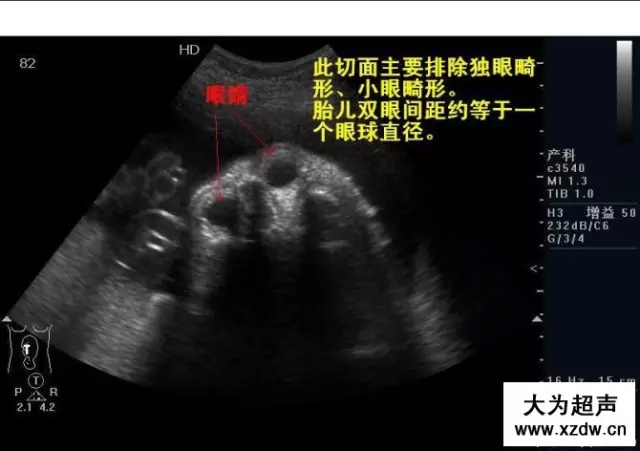

產科超聲正常圖片